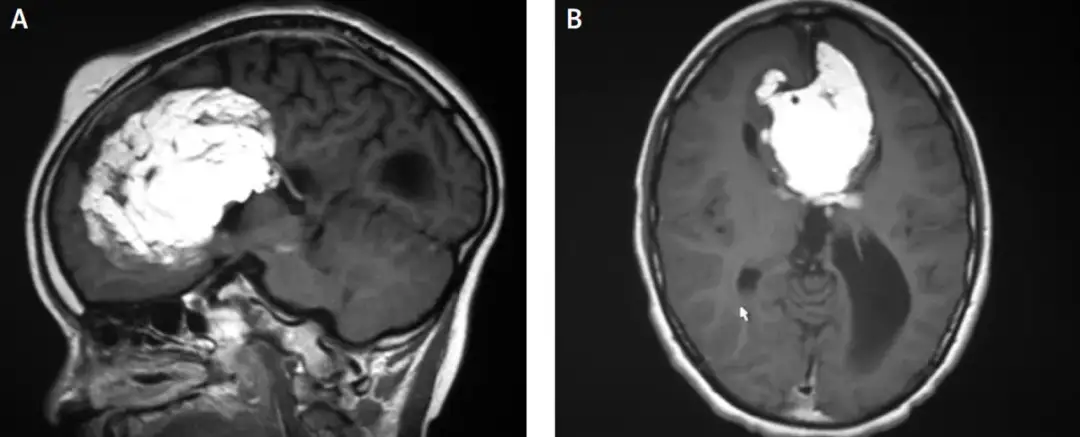

W diagnostyce zmian malacyjnych stosuje się różne badania neurologiczne, które są niezbędne do oceny stanu pacjenta. Najczęściej wykonuje się tomografię komputerową (TK) lub rezonans magnetyczny (RM), które pozwalają na dokładne zobrazowanie mózgu. Na przykład, podczas badania TK lekarz może szybko zidentyfikować obszary, w których wystąpiły zmiany malacyjne.

Inne testy, takie jak elektroencefalografia (EEG), mogą być również używane do oceny aktywności elektrycznej mózgu. To badanie jest szczególnie przydatne w diagnozowaniu napadów padaczkowych, które mogą wystąpić u pacjentów z uszkodzeniem mózgu. Warto pamiętać, że diagnostyka zmian w mózgu jest kluczowa dla ustalenia odpowiedniego leczenia i rehabilitacji.

| Rodzaj badania | Cel badania |

| Tomografia komputerowa (TK) | Obrazowanie struktury mózgu i identyfikacja zmian |

| Rezonans magnetyczny (RM) | Dokładne zobrazowanie tkanek mózgowych |

| Elektroencefalografia (EEG) | Ocena aktywności elektrycznej mózgu |